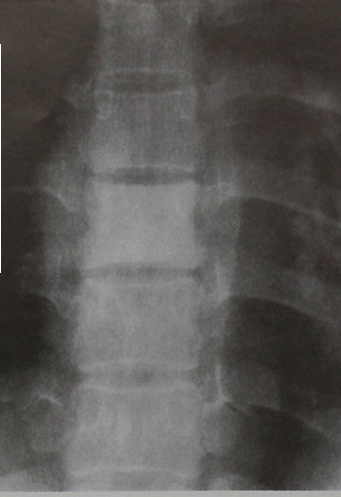

Диагностика лимфомы Ходжкина с помощью ПЭТ и КТ